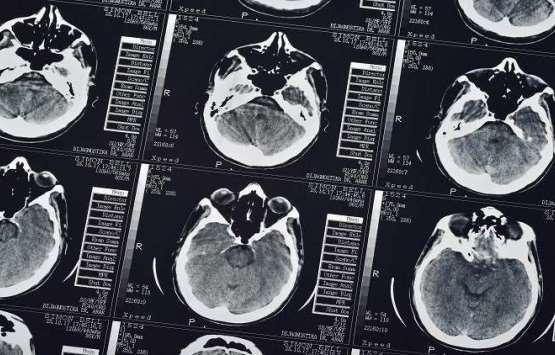

خبرني - اكتشف علماء معهد ماساتشوستس للتكنولوجيا منطقة خاصة في الدماغ تحفز الإنسان على التشاؤم وتمنعه من التفاعل مع أي شيء إيجابي.

وتضيف غريبل أن العلماء منذ القدم يحاولون ربط مناطق الدماغ بتكون مختلف المشاعر والأحاسيس، ومعرفة رد فعل الشخص على مختلف الأحداث في حياته وغير ذلك. وتمكنت مع فريقها العلمي من اكتشاف منطقة خاصة داخل ما يسمى الجسم المخطط وسط الدماغ، مسؤولة عن موازنة الإنسان لسلبيات وايجابيات أي مسألة أو قرار.